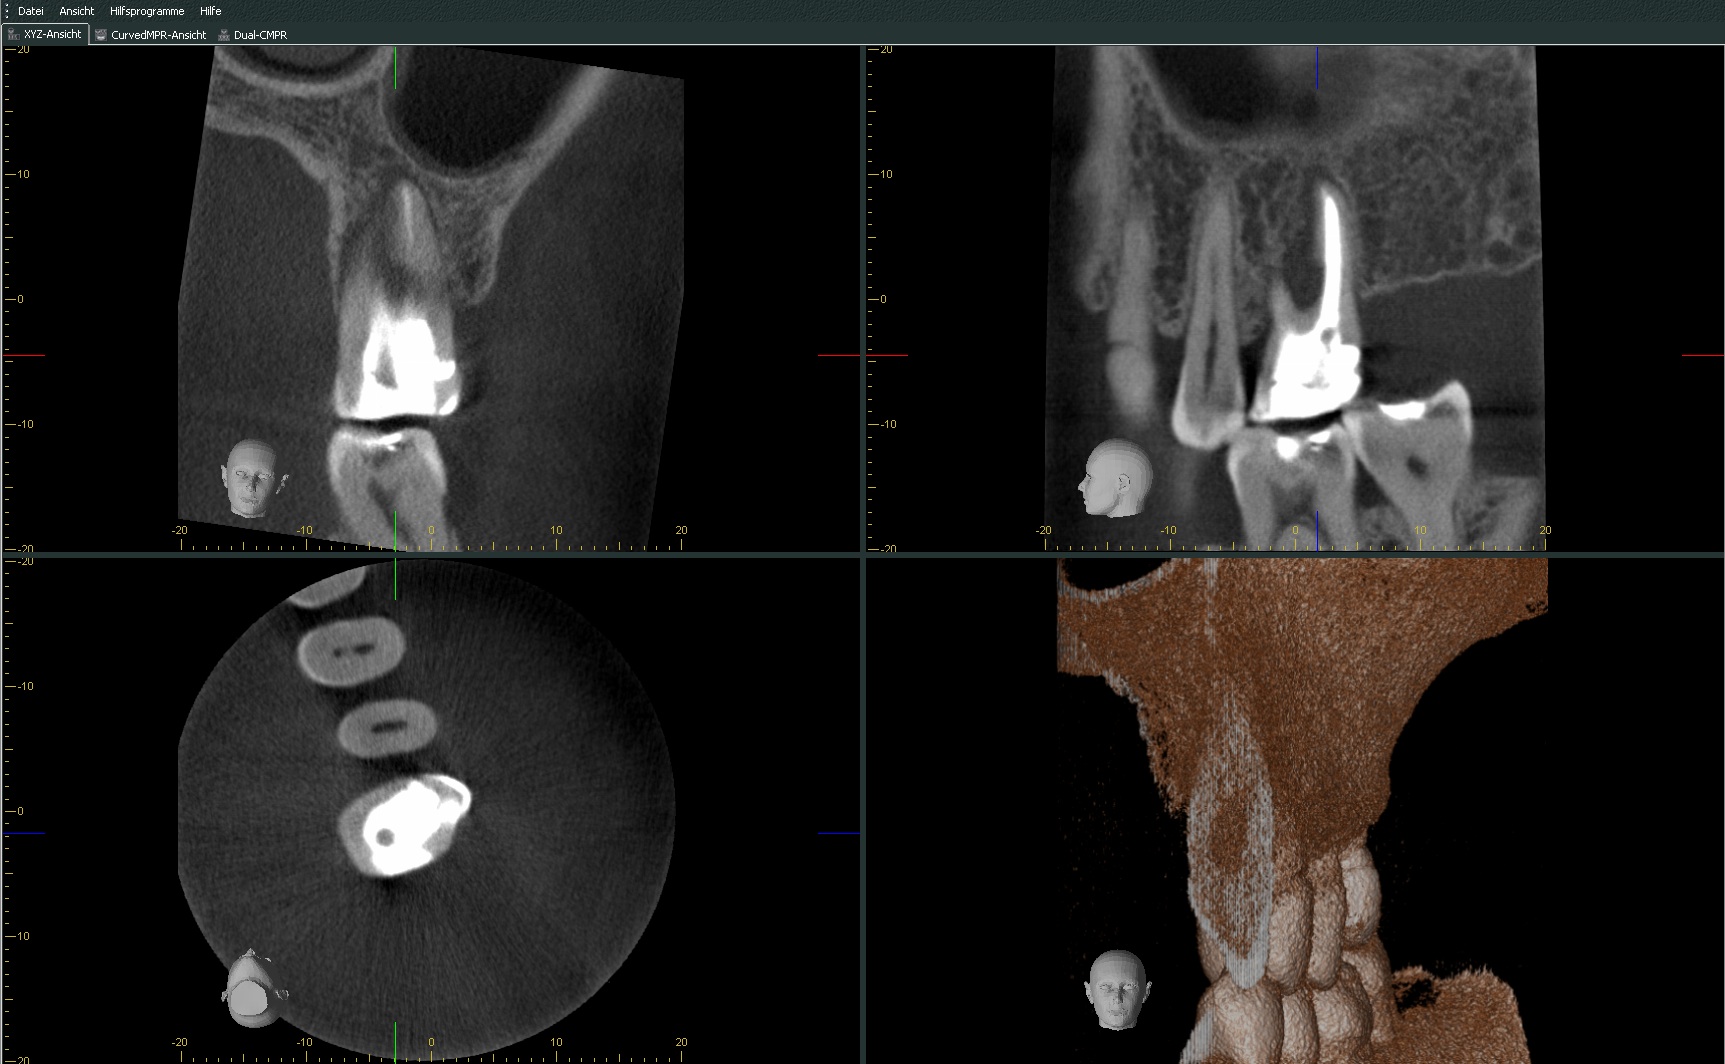

Diagnose gefragt?